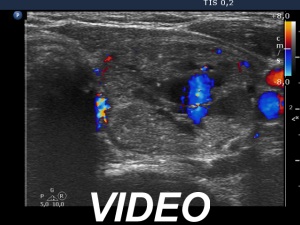

Eight mL bloody cystic fluid was aspirated. After I aspirated 4 mL fluid, I have noticed that the cyst began to refill at once and a few minutes later the cyst became as large as before the aspiration.

Suggestion: I did not perform sclerotherapy because of the lack of experience with at once refilling cysts. I'm not aware whether anyone had performed sclerotherapy in such cysts. A hormonal evaluation in 4 weeks was suggested.